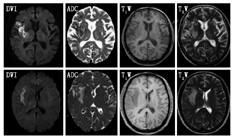

(1)腔隙性脑梗死:病灶直径3~15 mm,呈边缘清晰的圆形、裂隙状或椭圆形,MRI/T1WI呈低信号而T2WI呈高信号;急性期的DWI为高信号。陈旧性腔隙性脑梗死:在FLAIR上病灶呈低信号,周围有胶质增生的高信号。病灶主要分布于基底节、丘脑、内囊、豆状核和尾状核、脑干等脑穿支动脉供血区域。(2)多发性硬化:脑和脊髓均可有病灶,为多病灶,呈非对称性,通常有相对固定的分布模式及形态;病灶与侧脑室垂直分布;在T1WI为低信号,T2WI为高信号(煎蛋状、云雾状),FLAIR为高信号,急性期DWI呈高信号,增强后呈C形或开环状强化。

DWI:弥散加权成像;FLAIR:液体衰减反转恢复序列